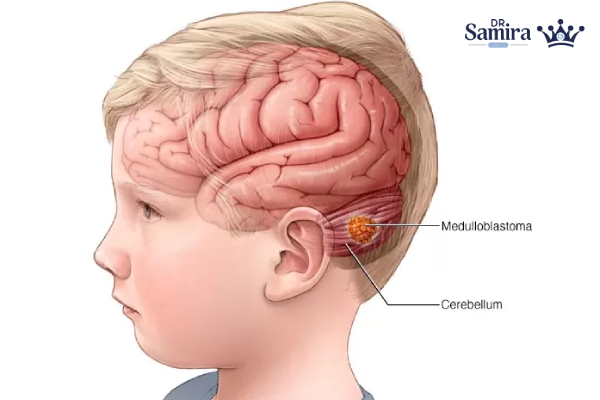

مدولوبلاستوم یک تومور بدخیم و سریعالرشد دستگاه عصبی مرکزی است که عمدتا در مخچه (ناحیه فوسای خلفی) ایجاد میشود و بهویژه در کودکان شایع است. این تومور در طبقهبندی سازمان جهانی بهداشت بهعنوان تومور درجه ۴ شناخته میشود، یعنی تمایل به رشد تهاجمی و انتشار از طریق مایع مغزی–نخاعی دارد. با وجود آزاردهنده بودن ماهیت بیماری، پیشرفتهای چند دهه اخیر در جراحی، پرتودرمانی و شیمیدرمانی، بقا را بهطور چشمگیری بهتر کردهاند و امروز درمانها بیش از گذشته «خطرمحور» و «زیرگروهمحور» شدهاند. در این مقاله، ابتدا به ماهیت و نشانههای مدولوبلاستوم میپردازیم، سپس تشخیص و طبقهبندیهای جدید مولکولی را مرور میکنیم و در نهایت درمان استاندارد، درمان در سنین خاص، رویکردهای عود و مسیرهای نوین درمانی را توضیح میدهیم.

مدولوبلاستوم از تومورهای «امبریونال» است؛ یعنی از سلولهای نابالغ عصبی منشأ میگیرد و بیشتر در مخچه شکل میگیرد؛ بخشی از مغز که هماهنگی حرکت و تعادل را کنترل میکند. بهدلیل موقعیت آن در فوسای خلفی، تومور میتواند مسیر جریان مایع مغزی–نخاعی را مسدود کرده و هیدروسفالی ایجاد کند. هرچند حدود 70٪ موارد در کودکان رخ میدهد، این بیماری در نوجوانان و بزرگسالان هم دیده میشود، اما الگوهای زیستی و پاسخ درمانی در بزرگسالان کمی متفاوت است.

تشخیص با MRI مغز و ستون فقرات آغاز میشود؛ MRI علاوه بر نشان دادن توده، امکان بررسی انتشار در مسیر مایع مغزی نخاعی را فراهم میکند. پس از جراحی، بررسی پاتولوژی و آزمایشهای مولکولی برای تعیین زیرگروه و خطر ضروری است. همچنین نمونهگیری از مایع مغزی نخاعی (وقتی از نظر بالینی امن باشد) برای یافتن سلولهای توموری به مرحلهبندی کمک میکند. این مرحلهبندی تعیین میکند که آیا بیماری محدود به مخچه است یا به سایر نواحی CNS پخش شده است.